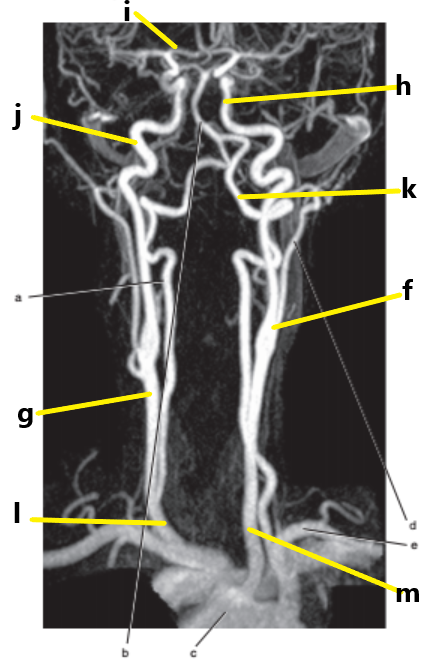

What is letter l ?

Common carotid

What is letter e ?

Subclavian artery

What is letter f ?

Common carotid artery

What is letter i ?

Anterior cerebral artery

What is letter m ?

What is letter j ?

Internal carotid artery

What is letter g ?

Vertebral artery

Aortic arch

What is letter b ?

What is letter k ?

Basilar artery